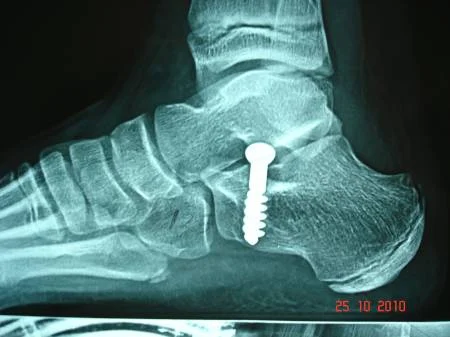

La colocación de una protesis especial en el calcáneo, acuta como "tope" para la corrección de la deformidad. Fabricada en acero inoxidable, cuenta con diferentes tamaños y longitudes de rosca.

La prótesis para el Pie Plano está diseñada para que actúe como "tope" y "eje" en el calcáneo, por lo que presenta una superficie pulimentada, como corresponde a la zona de roce. Fabricado en Acero Inoxidable, cuenta con diferentes tamaños y longitudes de rosca. Entre sus características más importantes, se encuentra el detalle de su cabeza, hexagonal y redondeada, así como su cuerpo cilíndrico.

Postoperatorio